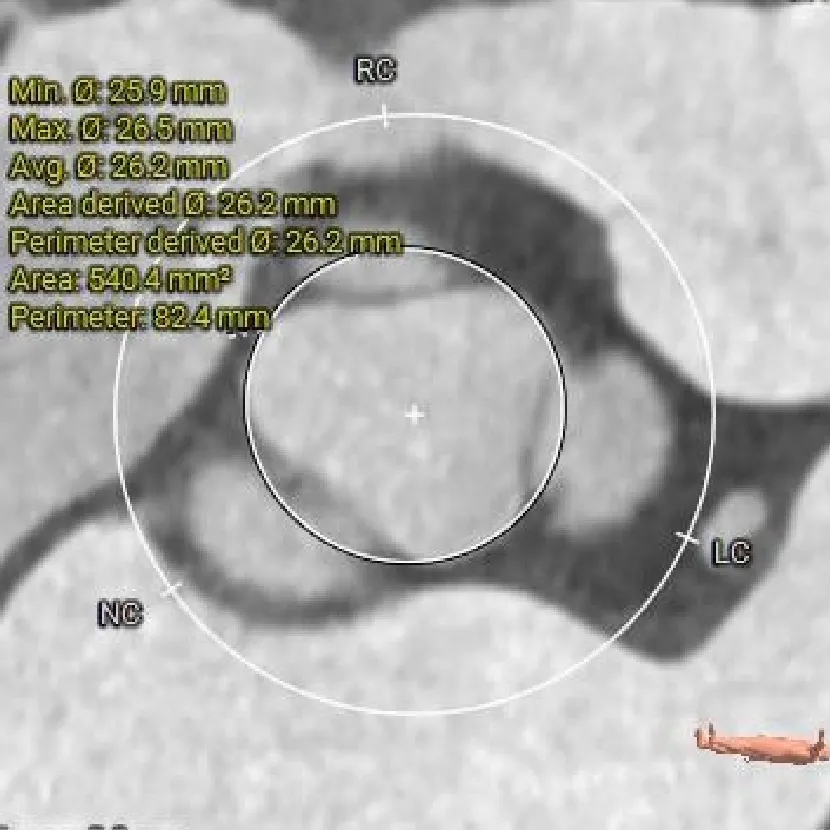

LVOT

26.2mm

瓣上结构测量

瓣上2mm

瓣上4mm

27.4mm

瓣上6mm

29.6mm

瓣上8mm

33.9mm